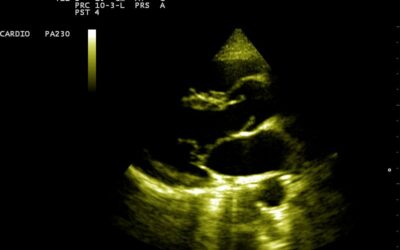

- Ecografie cardiaca bidimensionala si Doppler

Cardiomiopatie hipertrofica

Coarctatia